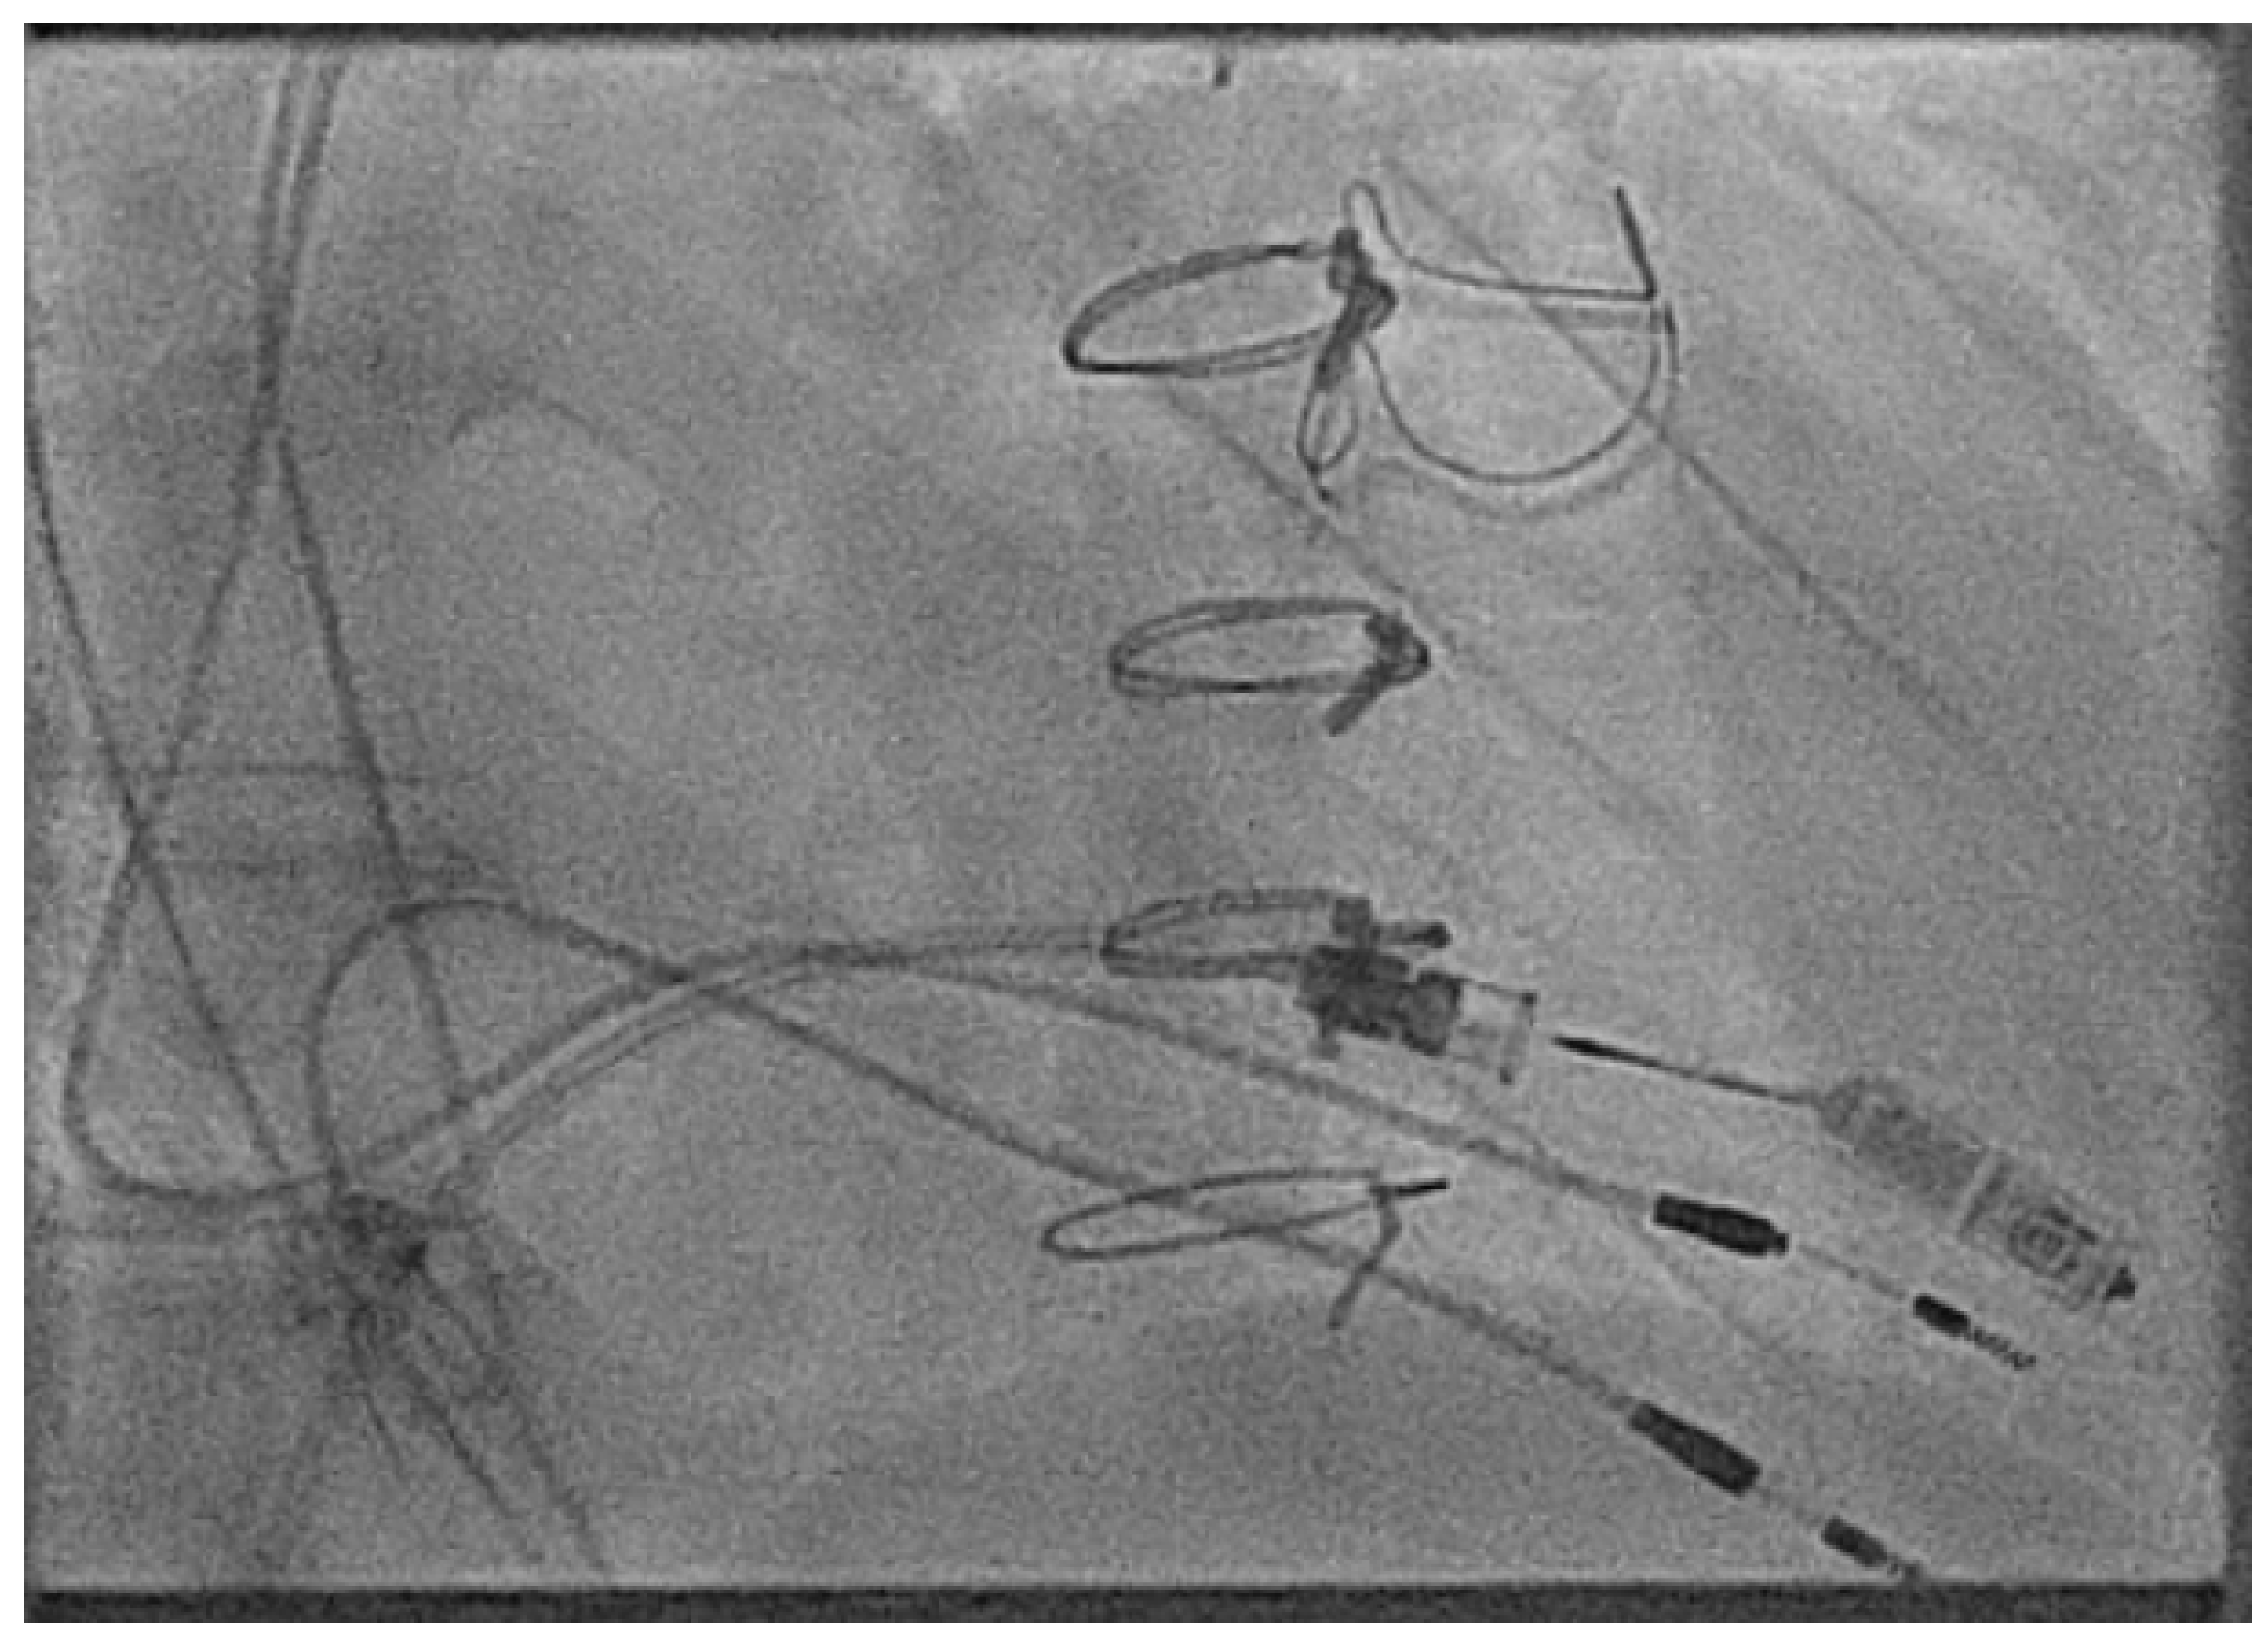

- Hayle, P.; Altayeb, F.; Hale, A.; Rao, A.; Ashrafi, R. Case report demonstrating novel approaches for leadless pacemaker implantation in the single ventricle heart. Eur. Heart J. Case Rep. 2025, 9, ytaf146. [Google Scholar] [CrossRef]

- Goulden, C.J.; Khanra, D.; Llewellyn, J.; Rao, A.; Evans, A.; Ashrafi, R. Novel approaches for leadless pacemaker implantation in the extra-cardiac Fontan cohort: Options to avoid leaded systems or epicardial pacing. J. Cardiovasc. Electrophysiol. 2023, 34, 2386–2392. [Google Scholar] [CrossRef]